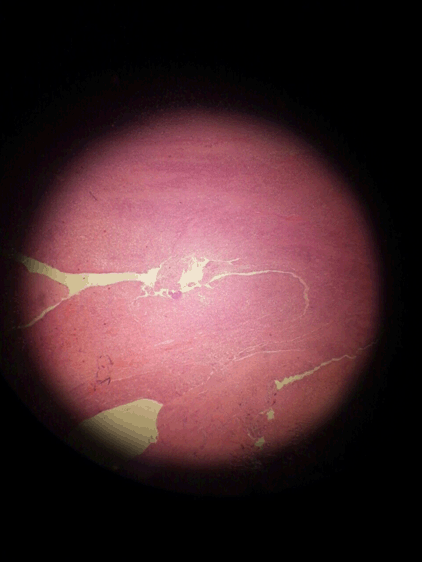

A 19-year-old male presented with a chronic nodule in the scalp for one year duration with intermittent discharge. There was no history of trauma. Local examination showed a single mobile nodule, 2x2 cm in size in the left parieto-occipital region with a punctum in center. Complete blood count, erythrocyte sedimentation rate and skull X-ray were normal. Complete excision of the nodule was performed under local anesthesia. Primary closure was done after irrigating the wound with diluted povidone. Histopathological examinations showed skin and subcutaneous tissue of scalp containing a sinus tract in the center infiltrated by mixed inflammatory cells, associated with foreign body giant cell reaction which contained hair particles. The wound showed clear margins after three months of the operation (Figure 1).

Figure 2: Histological confirmation of the scalp pilonidal sinus.